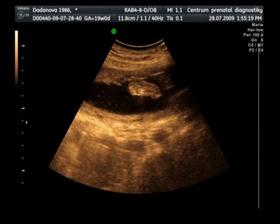

Naše maličké